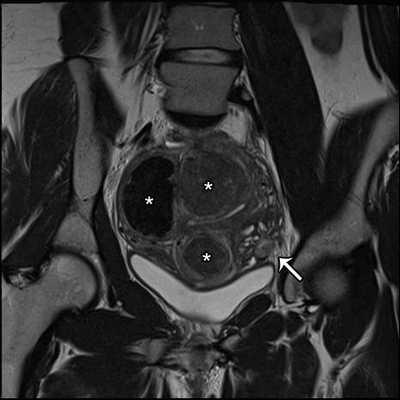

Аденомиоз выглядит как утолщение соединительной зоны образующее плохо отграниченную область низкой интенсивности сигнала, часто с гиперинтенсивными очагами на Т2-взвешенных изображениях. В основном локализуется в области дна, и, как правило, в задней стенке матки.

Выделяют две формы аденомиоза (рис.3):

1) диффузная: очаги аденомиоза распределены в пределах всего миометрия.

2) фокальная: очаги аденомиоза в миометрии присутствуют на ограниченном участке.Наиболее важным для диагностики аденомиоза признаком на МРТ является толщина переходной зоны более 12 мм. Толщина менее 8 мм, как правило, позволяет исключить диагноз.

При толщине переходной зоны от 8 до 12 мм, диагноз аденомиоза требует определенных вторичных критериев.

МРТ признаки аденомиоза:

![]()

Рис.3: Схематическое изображение и сагиттальные T2-взвешенные изображения нормальной постпубертатной матки (а), диффузного аденомиоза (b), фокального аденомиоза (с).

а) эндометрий однородно гиперинтенсивный, тонкая переходная зона имеет низкую интенсивность сигнала, наружный миометрий имеет промежуточную интенсивность сигнала; b) и с) аденомиоз матки с гипонтенсивным диффузным и фокальным расширением переходной зоны.

Рис.4: Диффузный аденомиоз: а) сагиттальные и b) корональные T2 изображения, показывающие утолщение переходной зоны c образованием плохо отграниченной области с низкой интенсивностью сигнала, точечными гиперинтенсивными включениями.